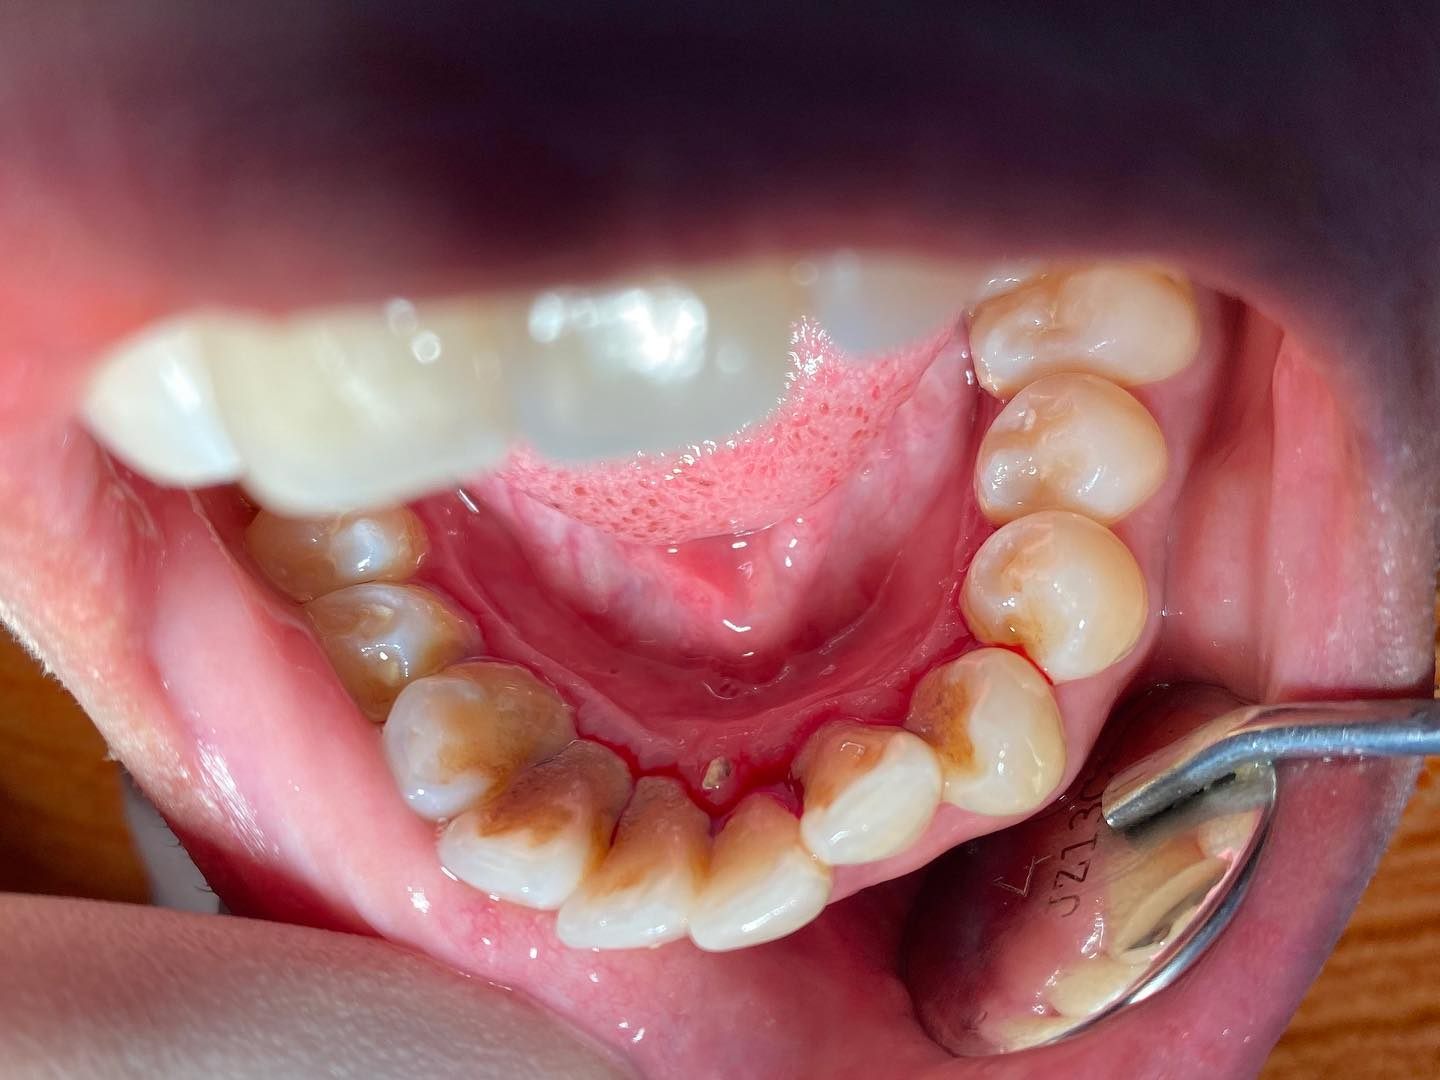

Jangan sangka gigi depan anda bersih, keseluruhan mulut pun bersih tau!

Tengok karang gigi tebal dekat belakang gigi tu ❌❌❌

Jangan ambil ringan dengan kebersihan gigi❗️ Karang gigi boleh menyebabkan banyak masalah gigi

❌gusi berdarah

❌nafas berbau

❌gigi sensitif

❌❌❌dan lebih teruk lagi, gigi akan goyang dan perlu dicabut.